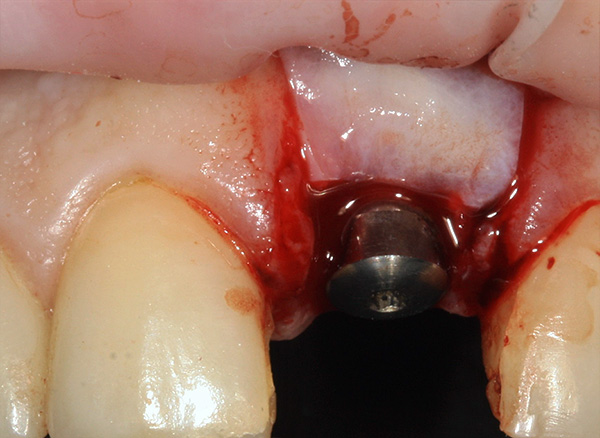

Em seguida, o retalho gengival é cortado e reclinado, um implante é inserido no orifício e o material ósseo granular é introduzido para a regeneração óssea: